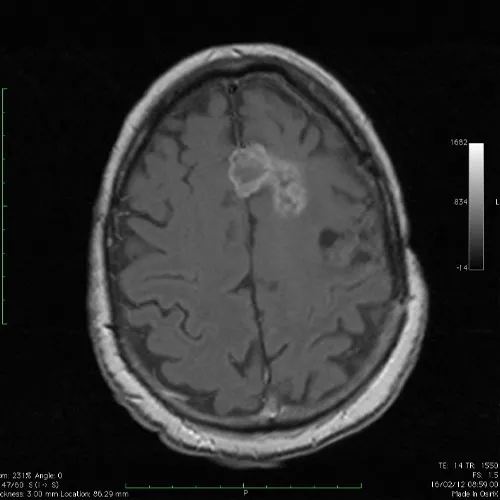

Metástasis cerebrales

Es considerada una complicación común en pacientes con cáncer avanzado y se estima que alrededor del 20-40% de los pacientes con cáncer desarrollarán metástasis cerebrales en algún momento de su enfermedad.

Gliomas cerebrales

Son un tipo de tumor que se origina en las células gliales del cerebro. Las células gliales son responsables de brindar soporte y nutrición a las neuronas y desempeñan un papel importante en el funcionamiento normal del sistema nervioso central.

Meningioma

Son tumores cerebrales que se originan en las meninges, las membranas que cubren el cerebro y la médula espinal. Estos tumores son generalmente benignos, lo que significa que no se propagan a otras partes del cuerpo, aunque en algunos casos pueden volverse malignos.

Cirugía Neurológica Radiocirugía/cirugía de Columna

16 años de experiencia en el tratamiento de tumores cerebrales y en el tratamiento de enfermedades de la columna, en instituciones del sector público y privado de México.